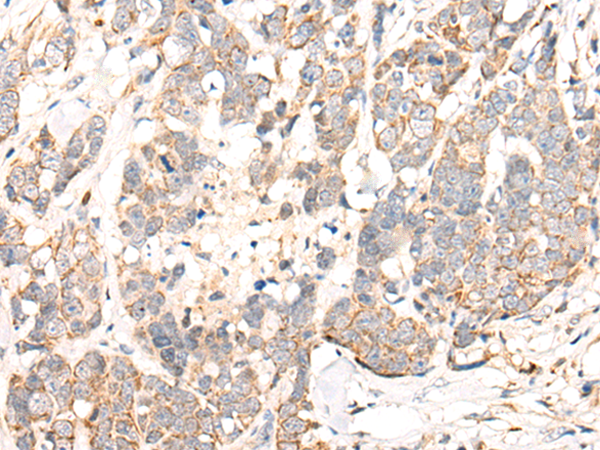

ELISA, IHC |

IHC positive control: |

Human liver cancer and human thyroid cancer |

IHC Recommend dilution: |

25-100 |